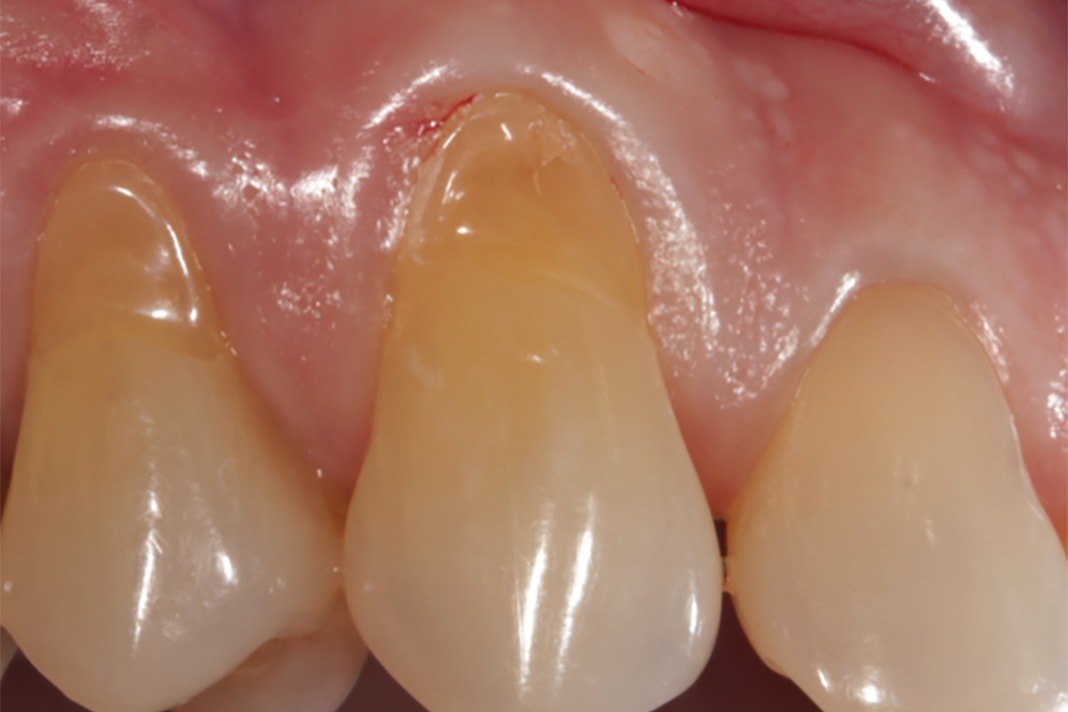

From www.jcda.ca

Unexpected Soft Tissue Changes in Response to Root Coverage Using an Orthodontic Gingival Recession a thin gingival biotype, presence of previous gr, baseline width of keratinized gingiva and facial gingival. isolated gingival recession may occur in as many as 30 per cent of adolescents, and lead to problems of dentine hypersensitivity,. several factors have been suggested to influence the occurrence of gingival recession following orthodontic. further randomized clinical studies including. Orthodontic Gingival Recession.